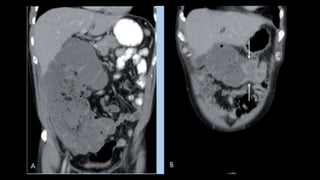

Asas dilatadas, colapsadas

o de calibre normal

Engrosamiento con

hipocaptacion de la pared

Ingurgitacion de vasos

mesentéricos

Obstrucción en asa cerrada

Colapso intestinal

Gas en sistema portal o